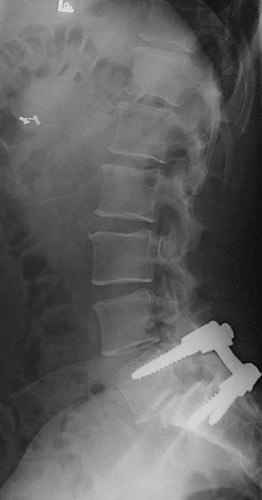

This radiograph of the spine demonstrates spondylolisthesis with slippage of the L5 vertebral body anterior to the S1 body. This can lead to spinal cord injury. In the radiograph below, internal screws have been placed to stabilize these vertebral bodies and prevent additional slippage at the site of spondylolisthesis. |